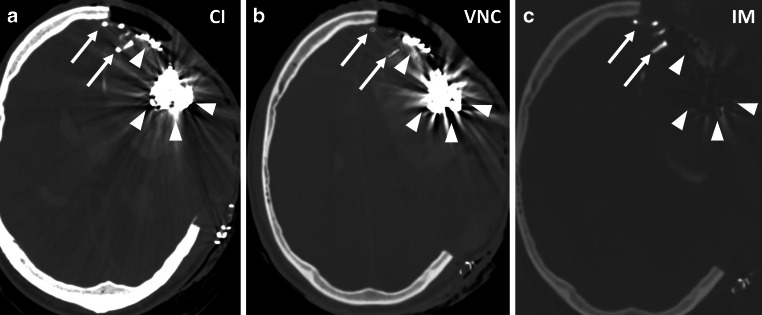

Methods: This retrospective study included 25 patients treated between April 2021 and March 2024, who underwent PCD-CT imaging post-embolization for intracranial arteriovenous malformations (AVM), dural arteriovenous fistulas (dAVF), spinal tumors, or middle meningeal artery (MMA) embolization for chronic subdural hematomas (cSDH). Imaging analysis involved iterative reconstruction, using conventional images (CI), iodine maps (IM), and virtual non-contrast (VNC) series. Two blinded neuroradiologists assessed the suppression quality of the embolic agents on a Likert scale.

Results: Of the 25 patients, 22 underwent intracranial and 3 spinal embolizations. The differentiation between iodine and tantalum-based embolics achieved 92% accuracy for reader 1 and 88% for reader 2, with a Cohen's kappa coefficient of 0.92 indicating high inter-reader agreement. Iodine-based agents were moderately suppressed, whereas tantalum-based agents exhibited superior suppression. Errors arose from mistaking suppressed platinum coils for tantalum-based embolics. Hemorrhage detection accuracy was high, with a Cohen's kappa of 0.92.